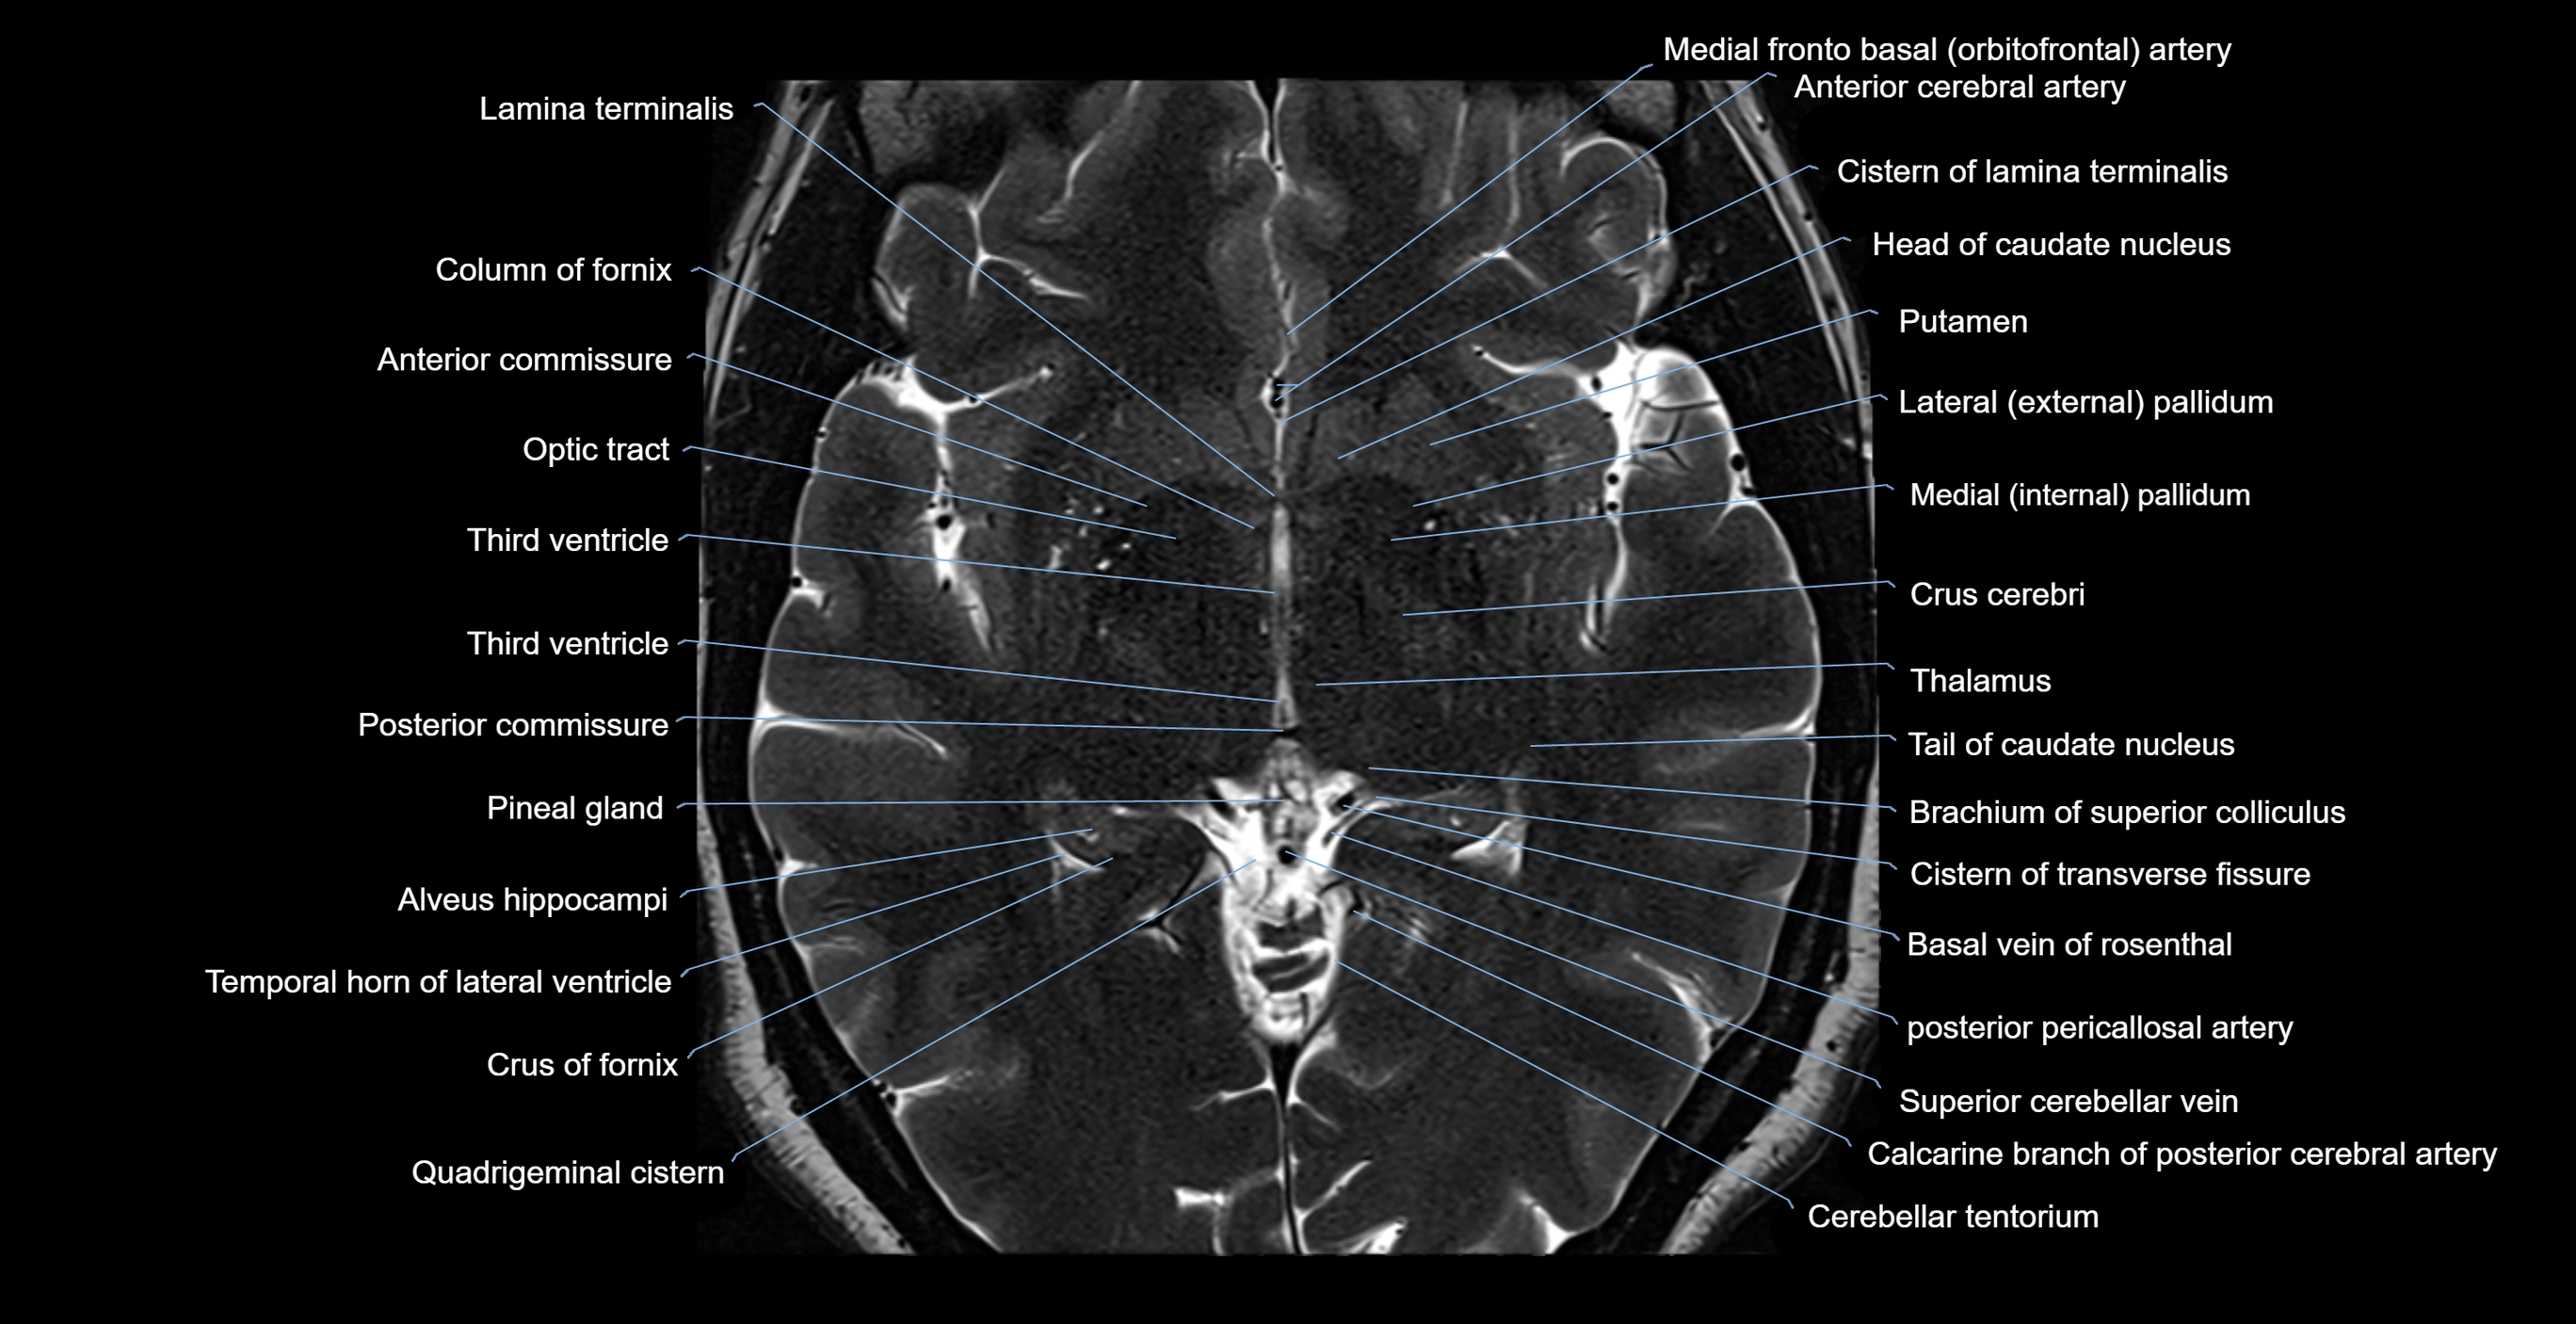

- Alveus

- Anterior cerebral artery

- Anterior commissure

- Basal vein of rosenthal

- Brachium of superior colliculus

- Calcarine branch of posterior cerebral artery

- Cerebellar tentorium

- Cistern of lamina terminalis

- Cistern of transverse fissure

- Column of fornix

- Crural cistern

- Crus cerebri

- Crus of fornix

- Head of caudate nucleus

- Lamina terminalis

- Mammillary body

- Medial frontobasal artery

- Medial pallidum

- Optic tract

- Pineal gland

- Posterior cerebral artery (P1 Segment)

- Posterior commissure

- Putamen

- Quadrigeminal cistern

- Superior cerebellar vein

- Tail of caudate nucleus

- Temporal horn of lateral ventricle

- Thalamus

- Third ventricle